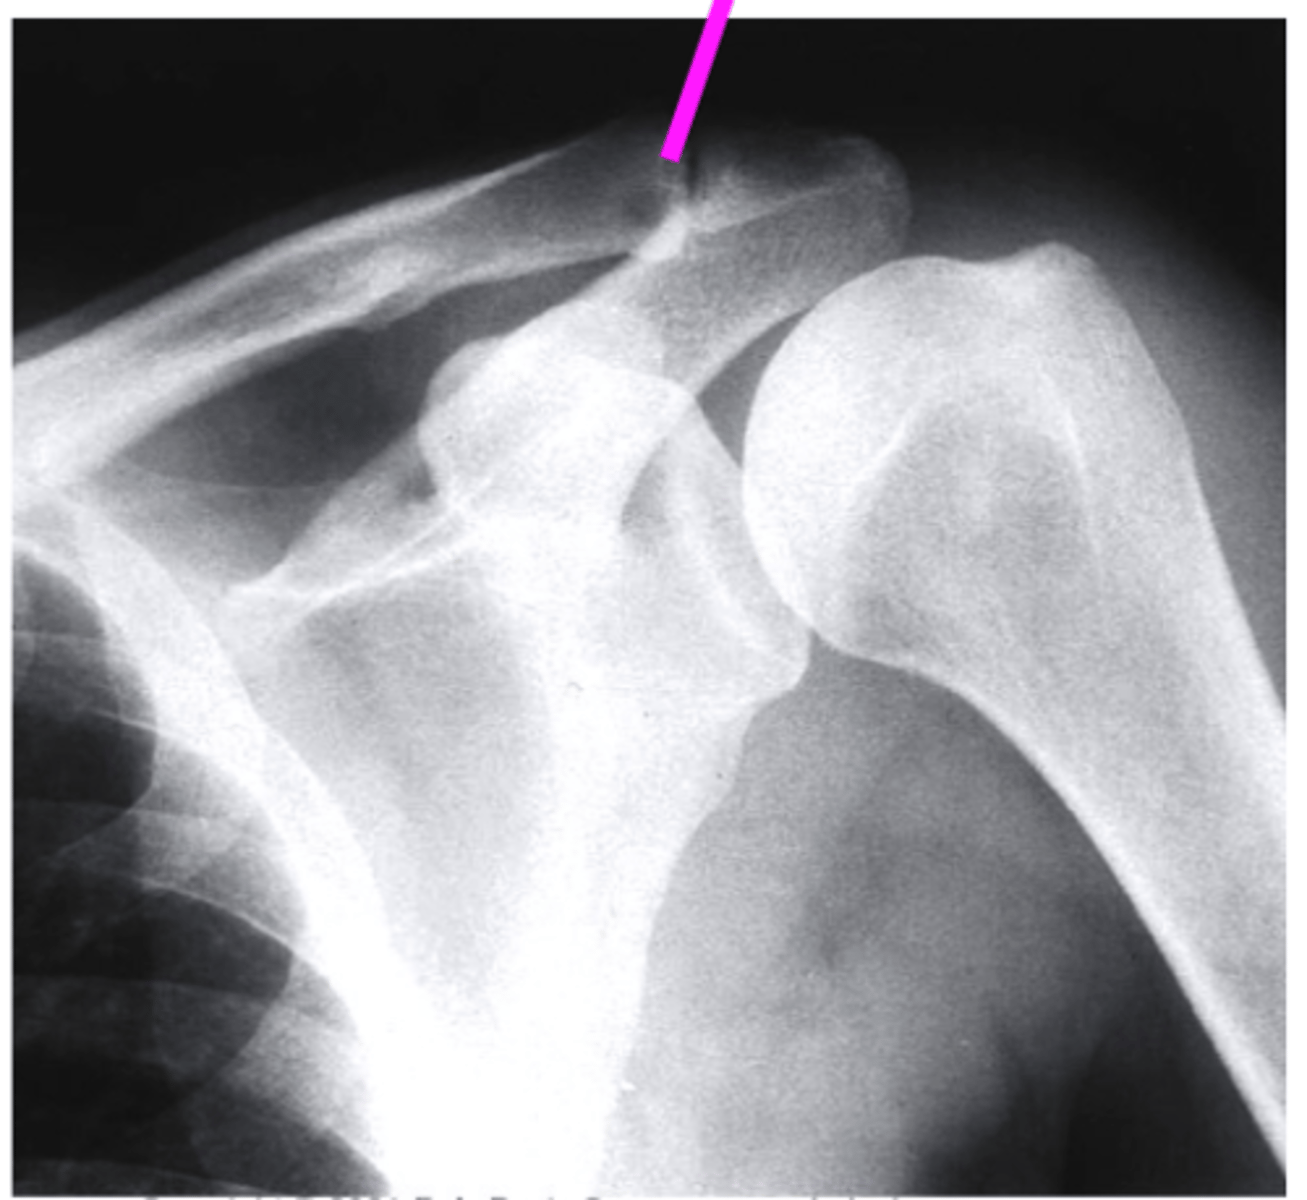

AP + IR

what view is this?

clavicle

what does the pink line point to?

spine of scapula

coracoid process

glenoid fossa of scapula

AC joint

acromion

Humeral Head

lesser tubercle